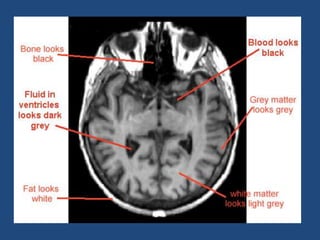

Relaxation Process 1-NMV recoversand realign to B0 this process called "T1 Recovery" 2-Nuclei loose Precessional coherence or dephase and NMV decay in the transverse plane this process called "T2 Decay"

T1 time &T2 Decay are an intrinsic contrast parameter that are inherent to tissue being imaged. T1WI